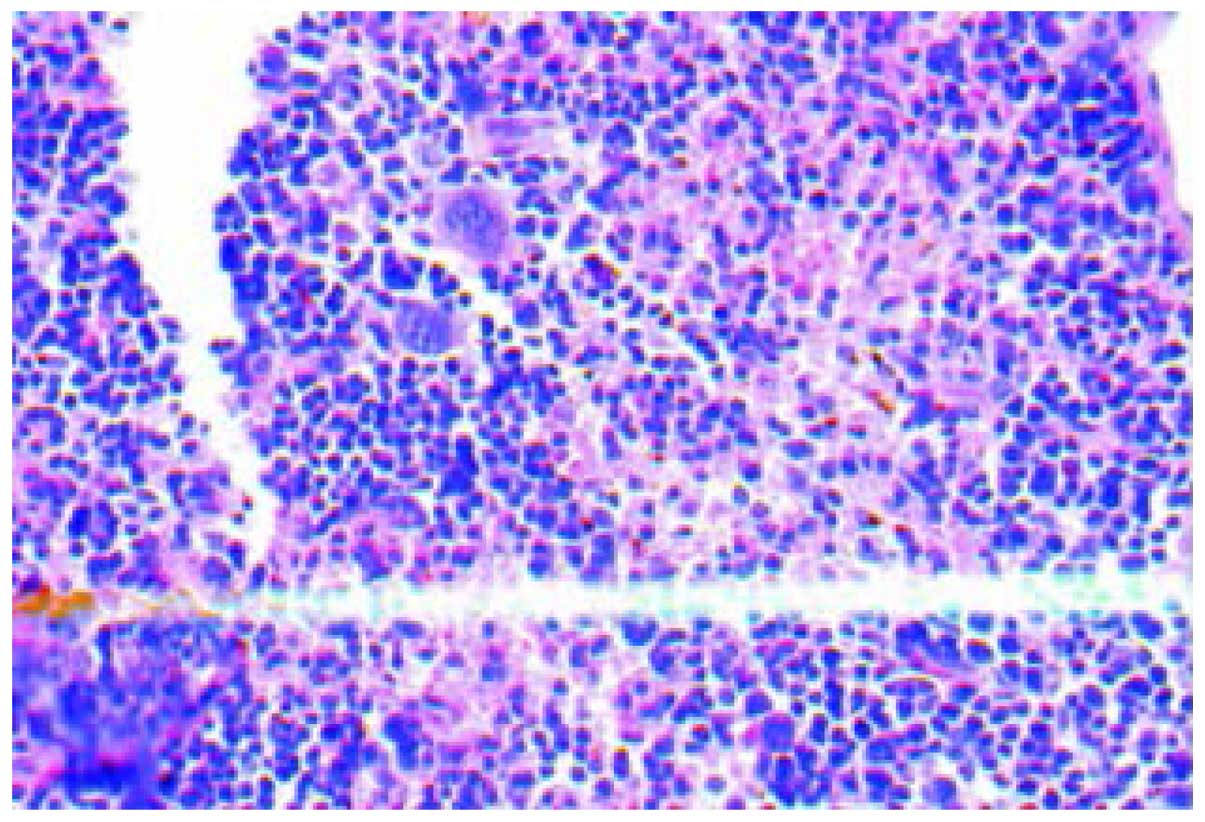

The H&E staining of tissues showed that inner liver metastatic tumors were clustered. The normal liver lobule structure was eradicated, cell volume was reduced, the cancer cell differentiation was poor with obvious atypia and the cytoplasm, karyopyknosis, karyorrhexis, dissolution and mitosis increased (Fig. 1). Various hoary nodes, with a diameter of 0.2–3 mm, were evident in part of the inoculated spleen. The tumor formation rate of orthotopic inoculation was 100%. The cancer cells of the spleen orthotopic inoculation were mainly distributed near the splenic sinusoids with obvious atypia, concentrated in the nucleus and cytoplasm, with the chromosomal becoming hard, and more intense staining (Fig. 2). The morphological structure of the liver metastases was similar to that of the tumor nodules of the spleen orthotopic inoculation, conforming to the structural features of colon low-differentiated adenocarcinoma.

Figure 1.

The liver metastases (hematoxylin and eosin; magnification, ×400). The image is from a representative mouse.